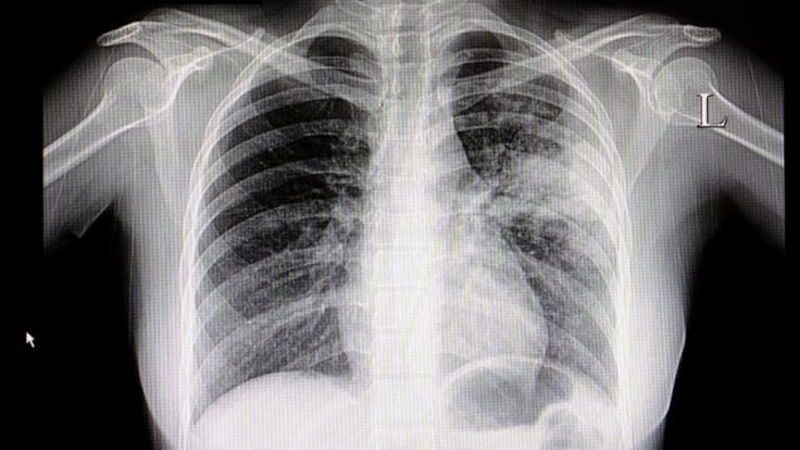

Strange Spike of Child Pneumonia Cases in China Likely Not a Novel Pathogen, Officials Say

An unusual surge of respiratory illness has been plaguing China in recent months, with increased cases of pneumonia affecting children in particular. Despite some early confusion, however, local health officials say these cases are not being caused by a novel germ. Instead, the surge is likely tied to a mix of known…